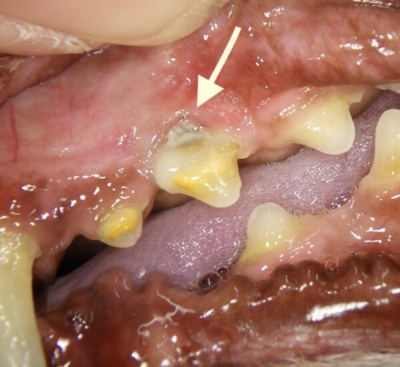

しかしよく観察すると、左上顎の第二前臼歯の歯肉が上がって根っこの部分が見えていました。(矢印部分)。この場所は歯根が鼻腔に近いため、歯周病が進行し歯の根元まで骨が失われると、鼻腔につながりかねません。その状態を口腔鼻腔ろうと言います。

左上顎の拡大図。矢印部分が歯肉が欠損しているところ